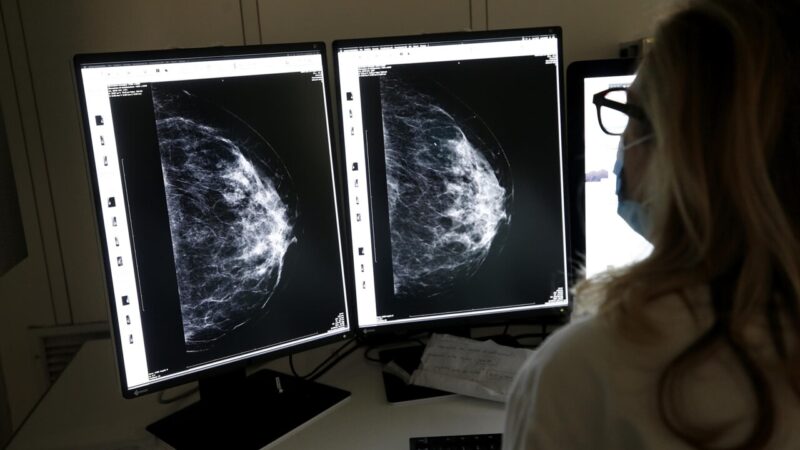

“Stiamo finalmente e fortunatamente assistendo a un fenomeno meraviglioso: una nuova e grande attenzione verso i controlli – afferma Francesco Caruso, direttore del dipartimento Oncologico – è ripresa la partecipazione agli screening istituzionali e, accanto a questi, crescono anche i controlli eseguiti su iniziativa personale. Quando una patologia viene identificata precocemente, il piano clinico cambia e cambia così anche la qualità di vita di una paziente, che dovrà affrontare non una massa difficilmente attaccabile, ma un tumore di più piccole dimensioni”.

“Oggi, oltre alla chemioterapia – sottolinea Caruso – disponiamo di terapie biologiche e immunoterapia che rappresentano un passo avanti importante. Questo, insieme al progresso della diagnostica e della chirurgia, ha contribuito a migliorare in modo netto la prognosi: nei dati riportati dalla letteratura, la sopravvivenza a dieci anni arriva all’88,6%, mentre trent’anni fa era intorno al 45/48%”.